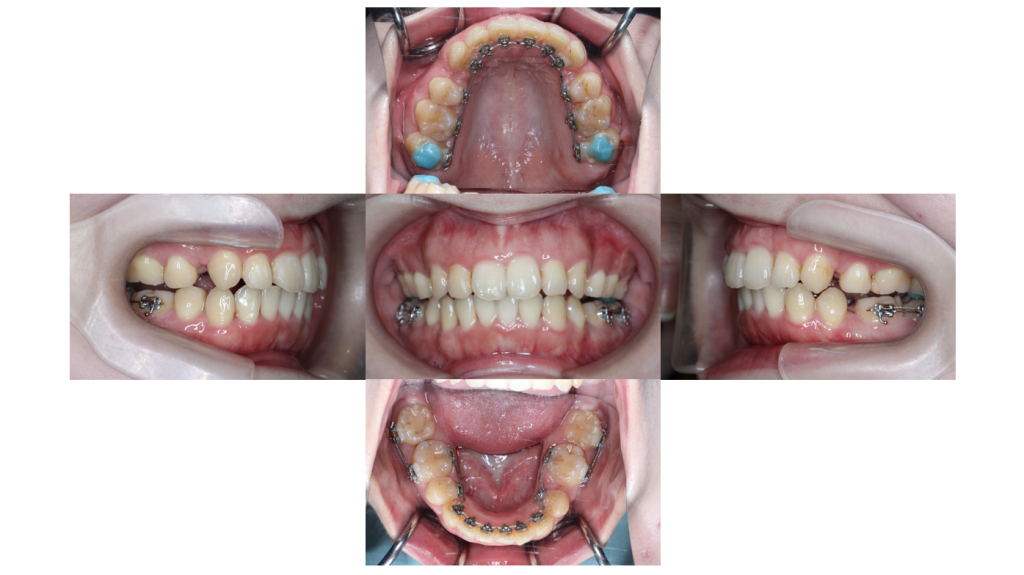

6ヶ月経過

叢生・裏側矯正の症例治療開始から約6ヶ月が経過し徐々に歯列がアーチに近づいてきました。